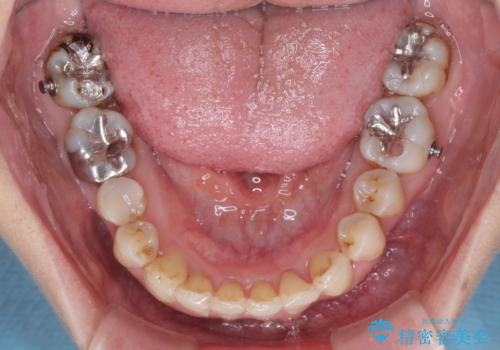

- 前歯の歯並びやむし歯治療の跡、奥歯の銀歯を気にして来院された患者様です。

インビザラインによる矯正治療の後に虫歯や銀歯をセラミックにて補綴することとしました。